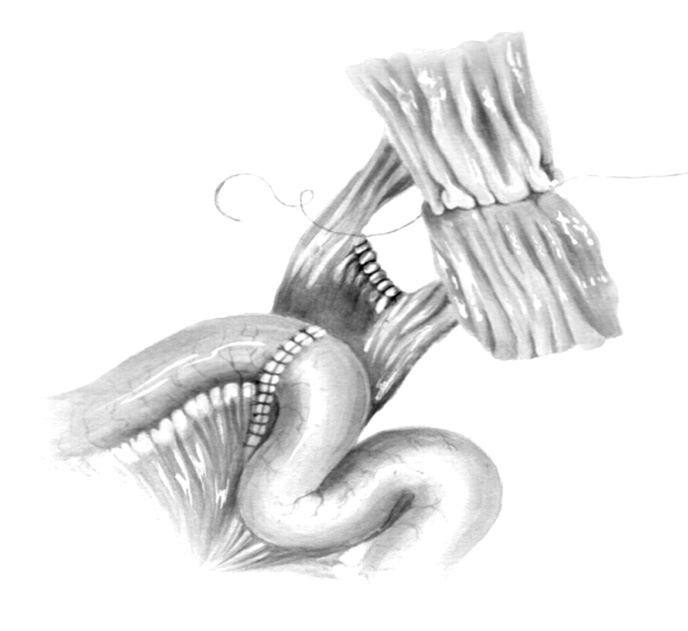

Small intestinal reconstruction of the ureters with reconfigured segments according to the Yang–Monti surgery was performed in 13 (6.7%) patients, including 8 (61.5%) with two intestinal segments, which allowed increasing the graft length to 10–12 cm. An important technical aspect of this ileoureteroplasty is the correct suturing of detubularized intestinal segments turned 90° toward each other. The reason was that after turning, the excess intestinal tissue appeared in the area of their connection, and the short mesenteries created tension and did not allow the resulting long intestinal strip to be straightened. If it is retubularized in this form, then corrugation and kinking of the newly formed intestinal tube occurs in the anastomosis area, which in the presence of excess tissue and edema in this area leads to graft obstruction (Fig. 1).

Fig. 1. Bending and corrugation in the anastomosis zone when stitching two reconfigured intestinal segments into a single ileotransplant

In this regard, this method was modified with a more reliable surgical technique (Patent for Invention No. 2681106, November 24, 2017). In this method, a 10–11 cm segment of the ileum was cut. Then, a 4-cm section in its central part was resected, with a shallow wedge-shaped excision of the remaining mesentery, which was unnecessary in this place (Fig. 2). As a result, the necessary space was created between the two resulting intestinal grafts for their positioning after reconfiguration. Then, both short ileografts were cut along the antimesenteric edges, turned 90° toward each other, and sutured with interrupted 3/0 vicryl sutures into a single longitudinal intestinal area 12 cm long and 3–3.5 cm wide (Figs. 3 and 4). In the central part, the elongated and turned ends of the grafts are located at the previously removed intestinal section. Therefore, in the area of their connection, tension in the mesenteries and bending of the graft associated with excess intestinal tissue were not observed. With subsequent retubularization, a smooth intestinal tube with a good lumen was formed on the intubator (Fig. 5), which was used to replace the ureteral defect (Fig. 6). Figure 7 presents contrasted multislice computed tomography for the patient 2 years after plastic surgery of the pelvic section of the right ureter using the method described above, who achieved good function of the right kidney and patency of the ureter and ileograft.

Fig. 2. Resection of the central part of the intestinal segment in order to create space for two lateral ileotransplants with their subsequent reconfiguration

Fig. 3. Two short ileotransplants are dissected along the anti-mesenteric edges and rotated 90° towards each other. At the top right, the removed central segment of the graft

Fig. 4. Two remaining intestinal sections (parts/pieces) are detubularized and stitched together